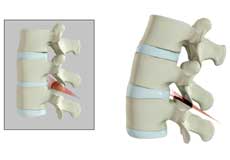

Herniated Disc (Lumbar)

Herniated disc is a condition in which the outer fibers (annulus) of the intervertebral disc are damaged causing the soft inner material of the nucleus pulposus to rupture out of its space. A herniated disc, common in the lower back (lumbar spine) occurs when there is a tear in the outer lining of the disc (annulus fibrosus). This causes the inner jelly-like material (nucleus pulposus) to leak out and place pressure on the adjacent spinal nerve root. It is the most common cause of lower back pain and pain that radiates down the leg (radiculopathy).

Lumbar Herniated Disc

A herniated disc is a condition in which the outer fibers (annulus) of the intervertebral disc are damaged, causing the soft inner material of the nucleus pulposus to rupture out of its space. It is the most common cause of lower back pain and pain that radiates down the leg (radiculopathy).

Lumbar Disc Herniation

Lumbar disc herniation is the most common cause of lower back pain and leg pain (sciatica). Aging, injury or trauma may cause the annulus fibrosus to tear, resulting in protrusion of the nucleus pulposus. This may compress the spinal nerves and/or spinal canal.

Disc Herniation

Disc herniation is a condition where the central nucleus pushes through the outer edge of the disc, causing a bulge that compresses the spinal nerves.